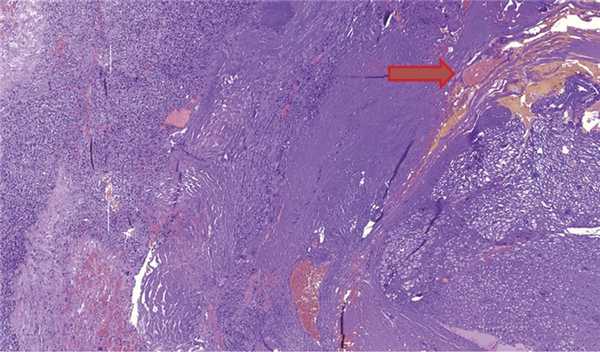

Гистологическое исследование (рис. 4) подтвердило микроскопический диагноз гемангиобластомы. Опухоль построена из двух типов клеток: стромальные клетки с оптически пустой цитоплазмой и большое количество сосудистых клеток. Опухоль окружена тонким слоем фиброзной ткани, к которой тесно прилежат фрагменты нервной ткани и скопления ганглиозных клеток (рис. 5).

Рис. 4. Гемангиобластома. Стромальные клетки с оптически пустой цитоплазмой (указано красной стрелкой) и сосудистые клетки (указано синей стрелкой). Окраска гематоксилином и эозином, ув. ×200. Рис. 5. Гемангиобластома (указано красной стрелкой) и скопления ганглиозных клеток (указано зеленой стрелкой). Окраска гематоксилином и эозином, ув. ×100.